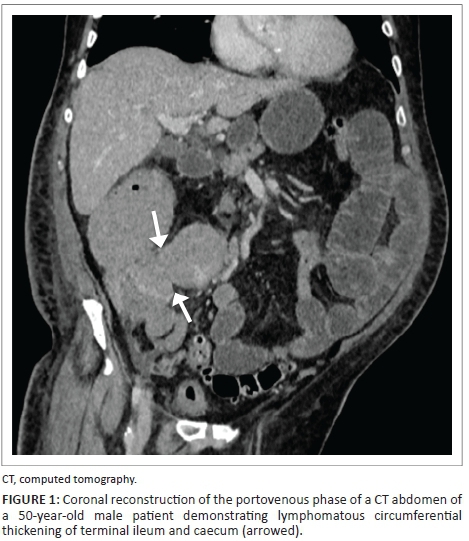

As demonstrated in Figures 1 and 2, there is lymphomatous infiltration of the ileocaecal valve, with circumferential thickening of the terminal ileum and caecum, lymphadenopathy and upstream small bowel dilatation. The patient was a 50-year-old male, with a CD4 count of 190 (cells/μL). Subsequent histological analysis following endoscopic biopsy confirmed the diagnosis of non-Hodgkin's lymphoma.

Small bowel lymphoma typically involves the terminal ileum, and becomes less frequent proximally.10

The radiological features of small bowel lymphoma include:

Focal thickening of the bowel wall, measuring between 1 and 7 cm9

Fungating masses

Tumour infiltration of the myenteric nerve plexus, resulting in aneurysmal bowel dilatation8

Solid mass lesion (rare).8